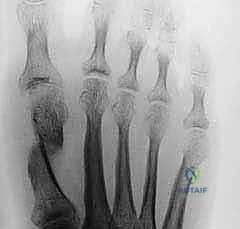

توضح هذه الصورة مدى الانحراف الشديد في مفصل إبهام القدم، وهو ما يستدعي تدخلاً جراحياً متقدماً مثل جراحة شفرون الممتدة لضمان عدم الانتكاس.

تعتبر الأشعة السينية أثناء الوقوف (تحمل الوزن) أداة التشخيص الأساسية. يقوم الأستاذ الدكتور محمد هطيف بقياس زاوية (HVA) وزاوية (IMA) بدقة لتحديد الخطة الجراحية المناسبة.